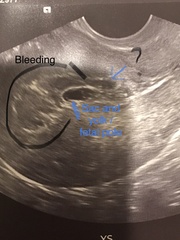

So here’s my scan from Xmas eve. Bleeding got worse and pain like period cramps. It’s not soaking through pads but get a trickle when I go to the loo. They said only measuring 5 weeks but i was 7+2 and couldn’t see a heartbeat. She said sac was a little too close to my C section scar which was worrying. I’ve tried to make sense of my ultrasound from what tech said but she said it was a pregnancy of uncertain viability and to return for a scan in 2 weeks. I went to a different EPU as mine couldn’t see me but I have an early scan already booked on the 2nd which will no doubt confirm the miscarriage

Can anyone make sense of my scan ?